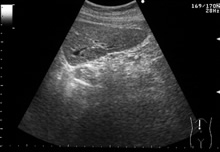

肝臓の正中縦断面のエコー像は、正常肝から、慢性肝炎、肝硬変に従って、断面の辺縁の鋭さが、鈍となり、肝硬変になると表面が凸凹不整となり、内部のきめが粗くなっていきます。

| 正常肝 | 慢性肝炎 | 肝硬変 |